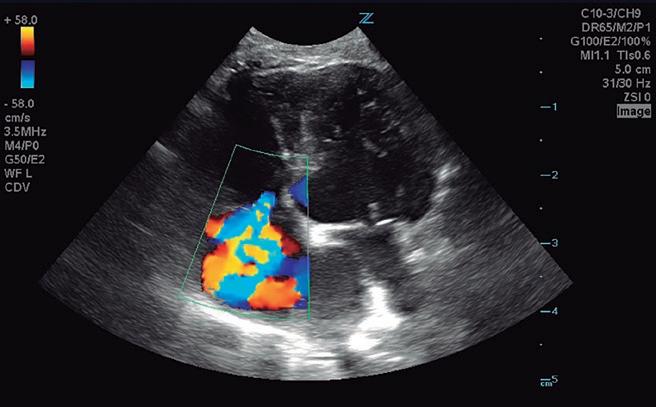

Bloqueantes de canales del calcio Hidralazina, nitratos e IECA